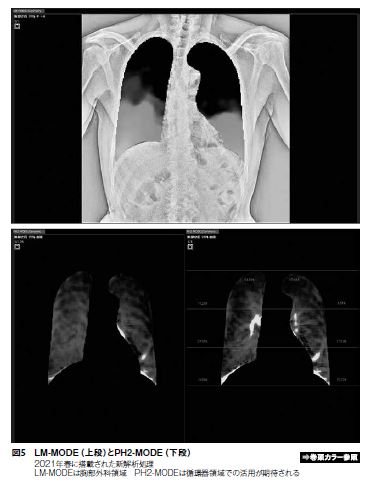

3. LM-MODE(図5)

肺野内の血管影などを含む信号値パターンを追跡し、呼吸に伴う各領域の移動量を計測することで、動きの低下領域を抽出し、動きの傾向をカラー表示にて1枚の解析画像にサマライズする。胸部手術前に肺の胸膜癒着を認識できる可能性がある。

7. PH2-MODE(図5)

心拍周期の肺野内信号値変化を抽出し、心拡張期のフレームを基準として各フレームからの差分値を計測しカラー表示する。また、解析した複数フレーム画像から1枚のMIP画像を生成できる。カラーの強弱から、血流量の定量評価ができる可能性がある。